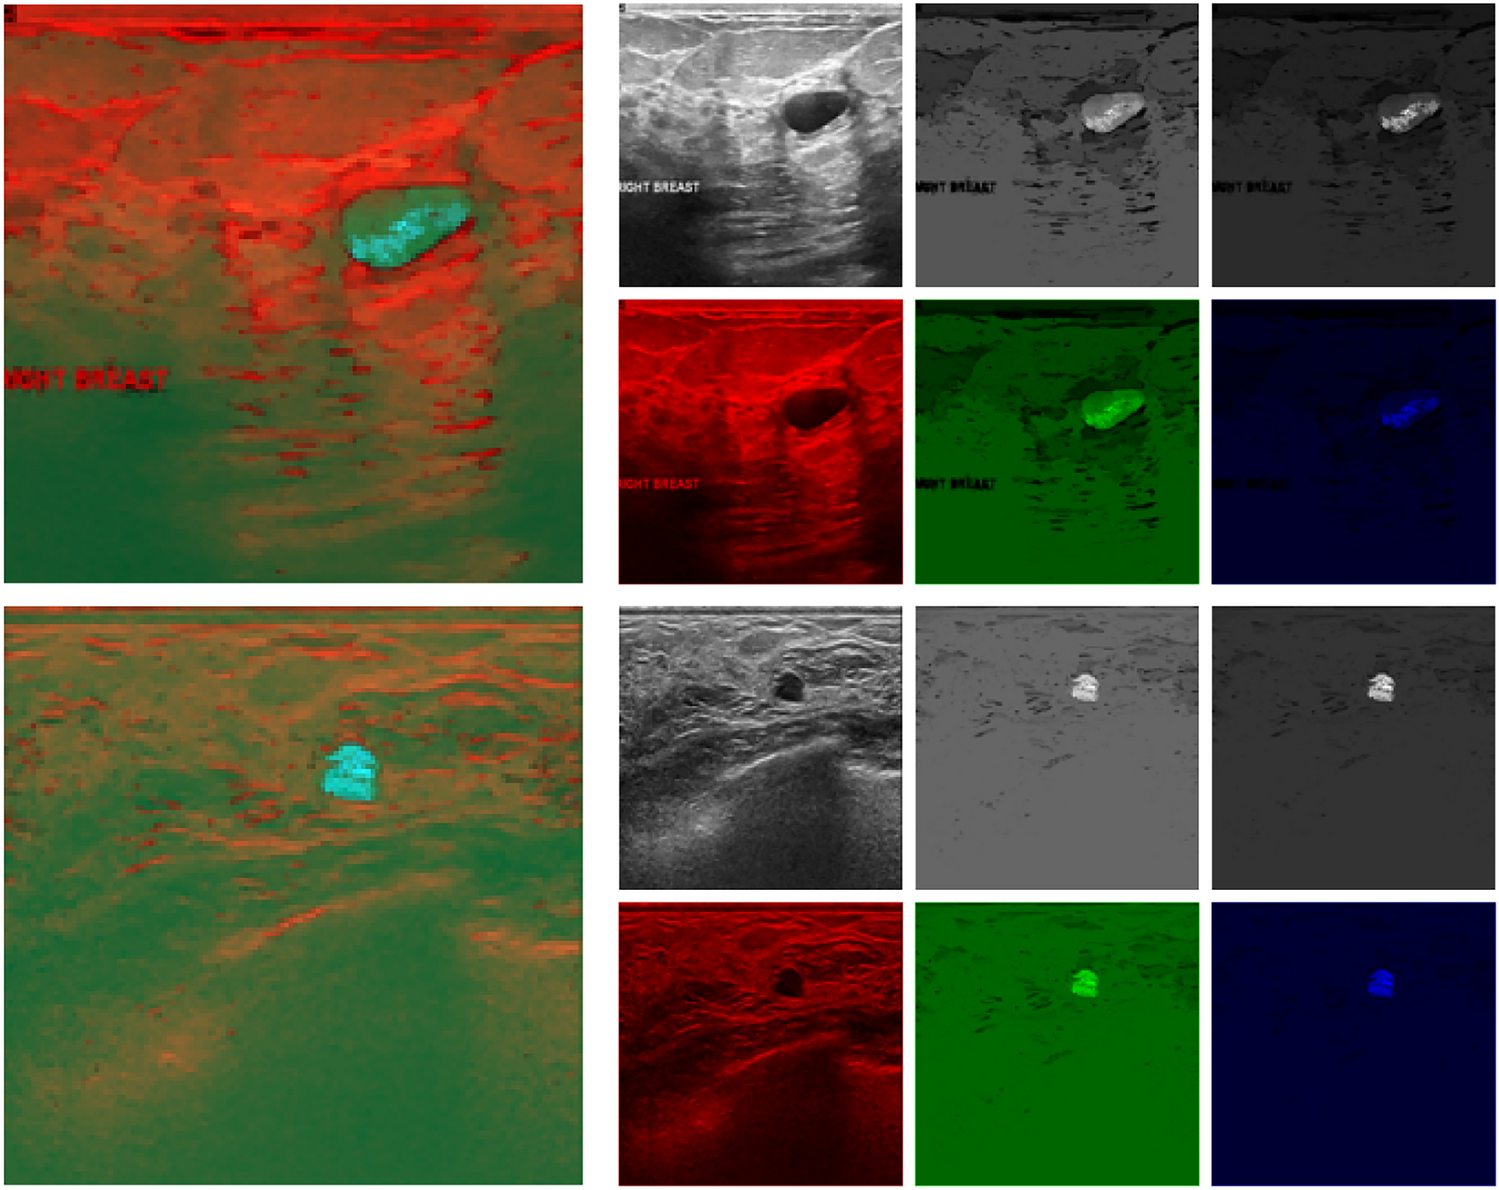

Fig. 3

Illustration of hybrid pseudo-color images. In each of the two cases, the hybrid image is shown on the left, and its components are on the right (left to right: the original US image and two fuzzy connectivity scenes (\({\textbf {W}}_{1}\) and \({\textbf {W}}_{2}\), respectively) as grayscale images above, and mapped to the appropriate chromatic channel below).